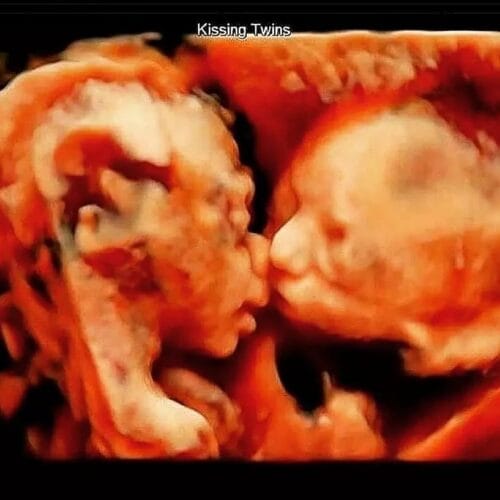

Σε 4D υπερηχογράφημα αποτυπώνεται η στιγμή που το ένα διδυμάκι φιλάει το άλλο

Σε 4D υπερηχογράφημα αποτυπώνεται η στιγμή που το ένα διδυμάκι φιλάει το άλλο! Τα δίδυμα είναι το διπλό δώρο της ζωής που από την πρώτη μέρα της σύλληψης ενώνονται με έναν ισχυρό δεσμό που θα διαρκέσει για πάντα. Αυτός ο αόρατος δεσμός είναι η πεμπτουσία της ύπαρξης των διδύμων καθώς είναι μια γροθιά, αγαπημένα και […]